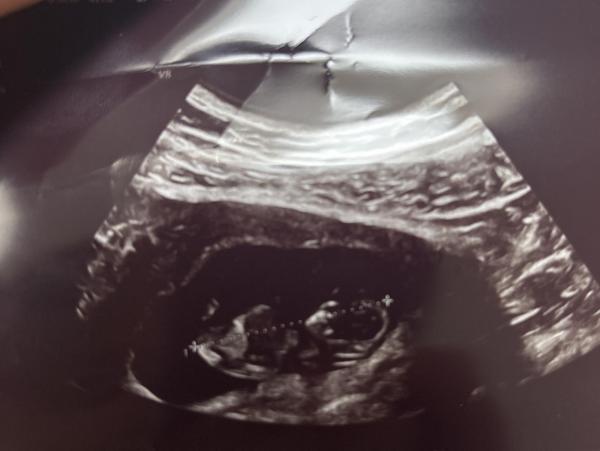

Hey kennt sich jemand mit NUB oder Ramzi aus? Es ist mein 2. Kind und ich wusste bei dem ersten oh das wird ein Junge, habe mich von meinem Mann überzeugen lassen es wird ein Mädchen tatdaaaa es wurde ein Junge & Als ich den Test gemacht habe und den 2. Strich gesehen habe dachte ich direkt ohhhh ich kann Kleidchen kaufen jetzt meine Frage was denkt ihr welches Geschlecht es ist? 1. Bild SSW 7+4 2. + 3. Bild SSW 10+5

Bild zu NUB oder Ramzi - Forum für Juni - Mamis